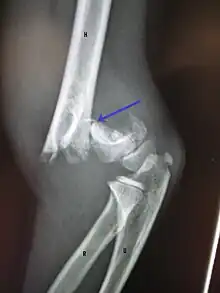

Distal humerus fractures usually occur as a result of physical trauma to the elbow region. If the elbow is bent during the trauma, then the olecranon is driven upward, producing a T- or Y-shaped fracture or displacing one of the condyles.[7]

Definitive diagnosis of humerus fractures is typically made through radiographic imaging. For proximal fractures, X-rays can be taken from a scapular anteroposterior (AP) view, which takes an image of the front of the shoulder region from an angle, a scapular Y view, which takes an image of the back of the shoulder region from an angle, and an axillar lateral view, which has the patient lie on his or her back, lift the bottom half of the arm up to the side, and have an image taken of the axilla region underneath the shoulder.[9] Fractures of the humerus shaft are usually correctly identified with radiographic images taken from the AP and lateral viewpoints.[12] Damage to the radial nerve from a shaft fracture can be identified by an inability to bend the hand backwards or by decreased sensation in the back of the hand.[5] Images of the distal region are often of poor quality due to the patient being unable to extend the elbow because of pain. If a severe distal fracture is suspected, then a computed tomography (CT) scan can provide greater detail of the fracture. Nondisplaced distal fractures may not be directly visible; they may only be visible due to fat being displaced because of internal bleeding in the elbow.[7]

Fractures of the humerus are classified based on the location of the fracture and then by the type of fracture. There are three locations that humerus fractures occur: at the proximal location, which is the top of the humerus near the shoulder, in the middle, which is at the shaft of the humerus, and the distal location, which is the bottom of the humerus near the elbow.[9] Proximal fractures are classified into one of four types of fractures based on the displacement of the greater tubercle, the lesser tubercle, the surgical neck, and the anatomical neck, which are the four parts of the proximal humerus, with fracture displacement being defined as at least one centimeter of separation or an angulation greater than 45 degrees. One-part fractures involve no displacement of any parts of the humerus, two-part fractures have one part displaced relative to the other three; three-part fractures have two displaced fragments, and four-part fractures have all fragments displaced from each other.[13][14][3] Fractures of the humerus shaft are subdivided into transverse fractures, spiral fractures, "butterfly" fractures, which are a combination of transverse and spiral fractures, and pathological fractures, which are fractures caused by medical conditions.[12] Distal fractures are split between supracondylar fractures, which are transverse fractures above the two condyles at the bottom of the humerus, and intercondylar fractures, which involve a T- or Y-shaped fracture that splits the condyles.[7]